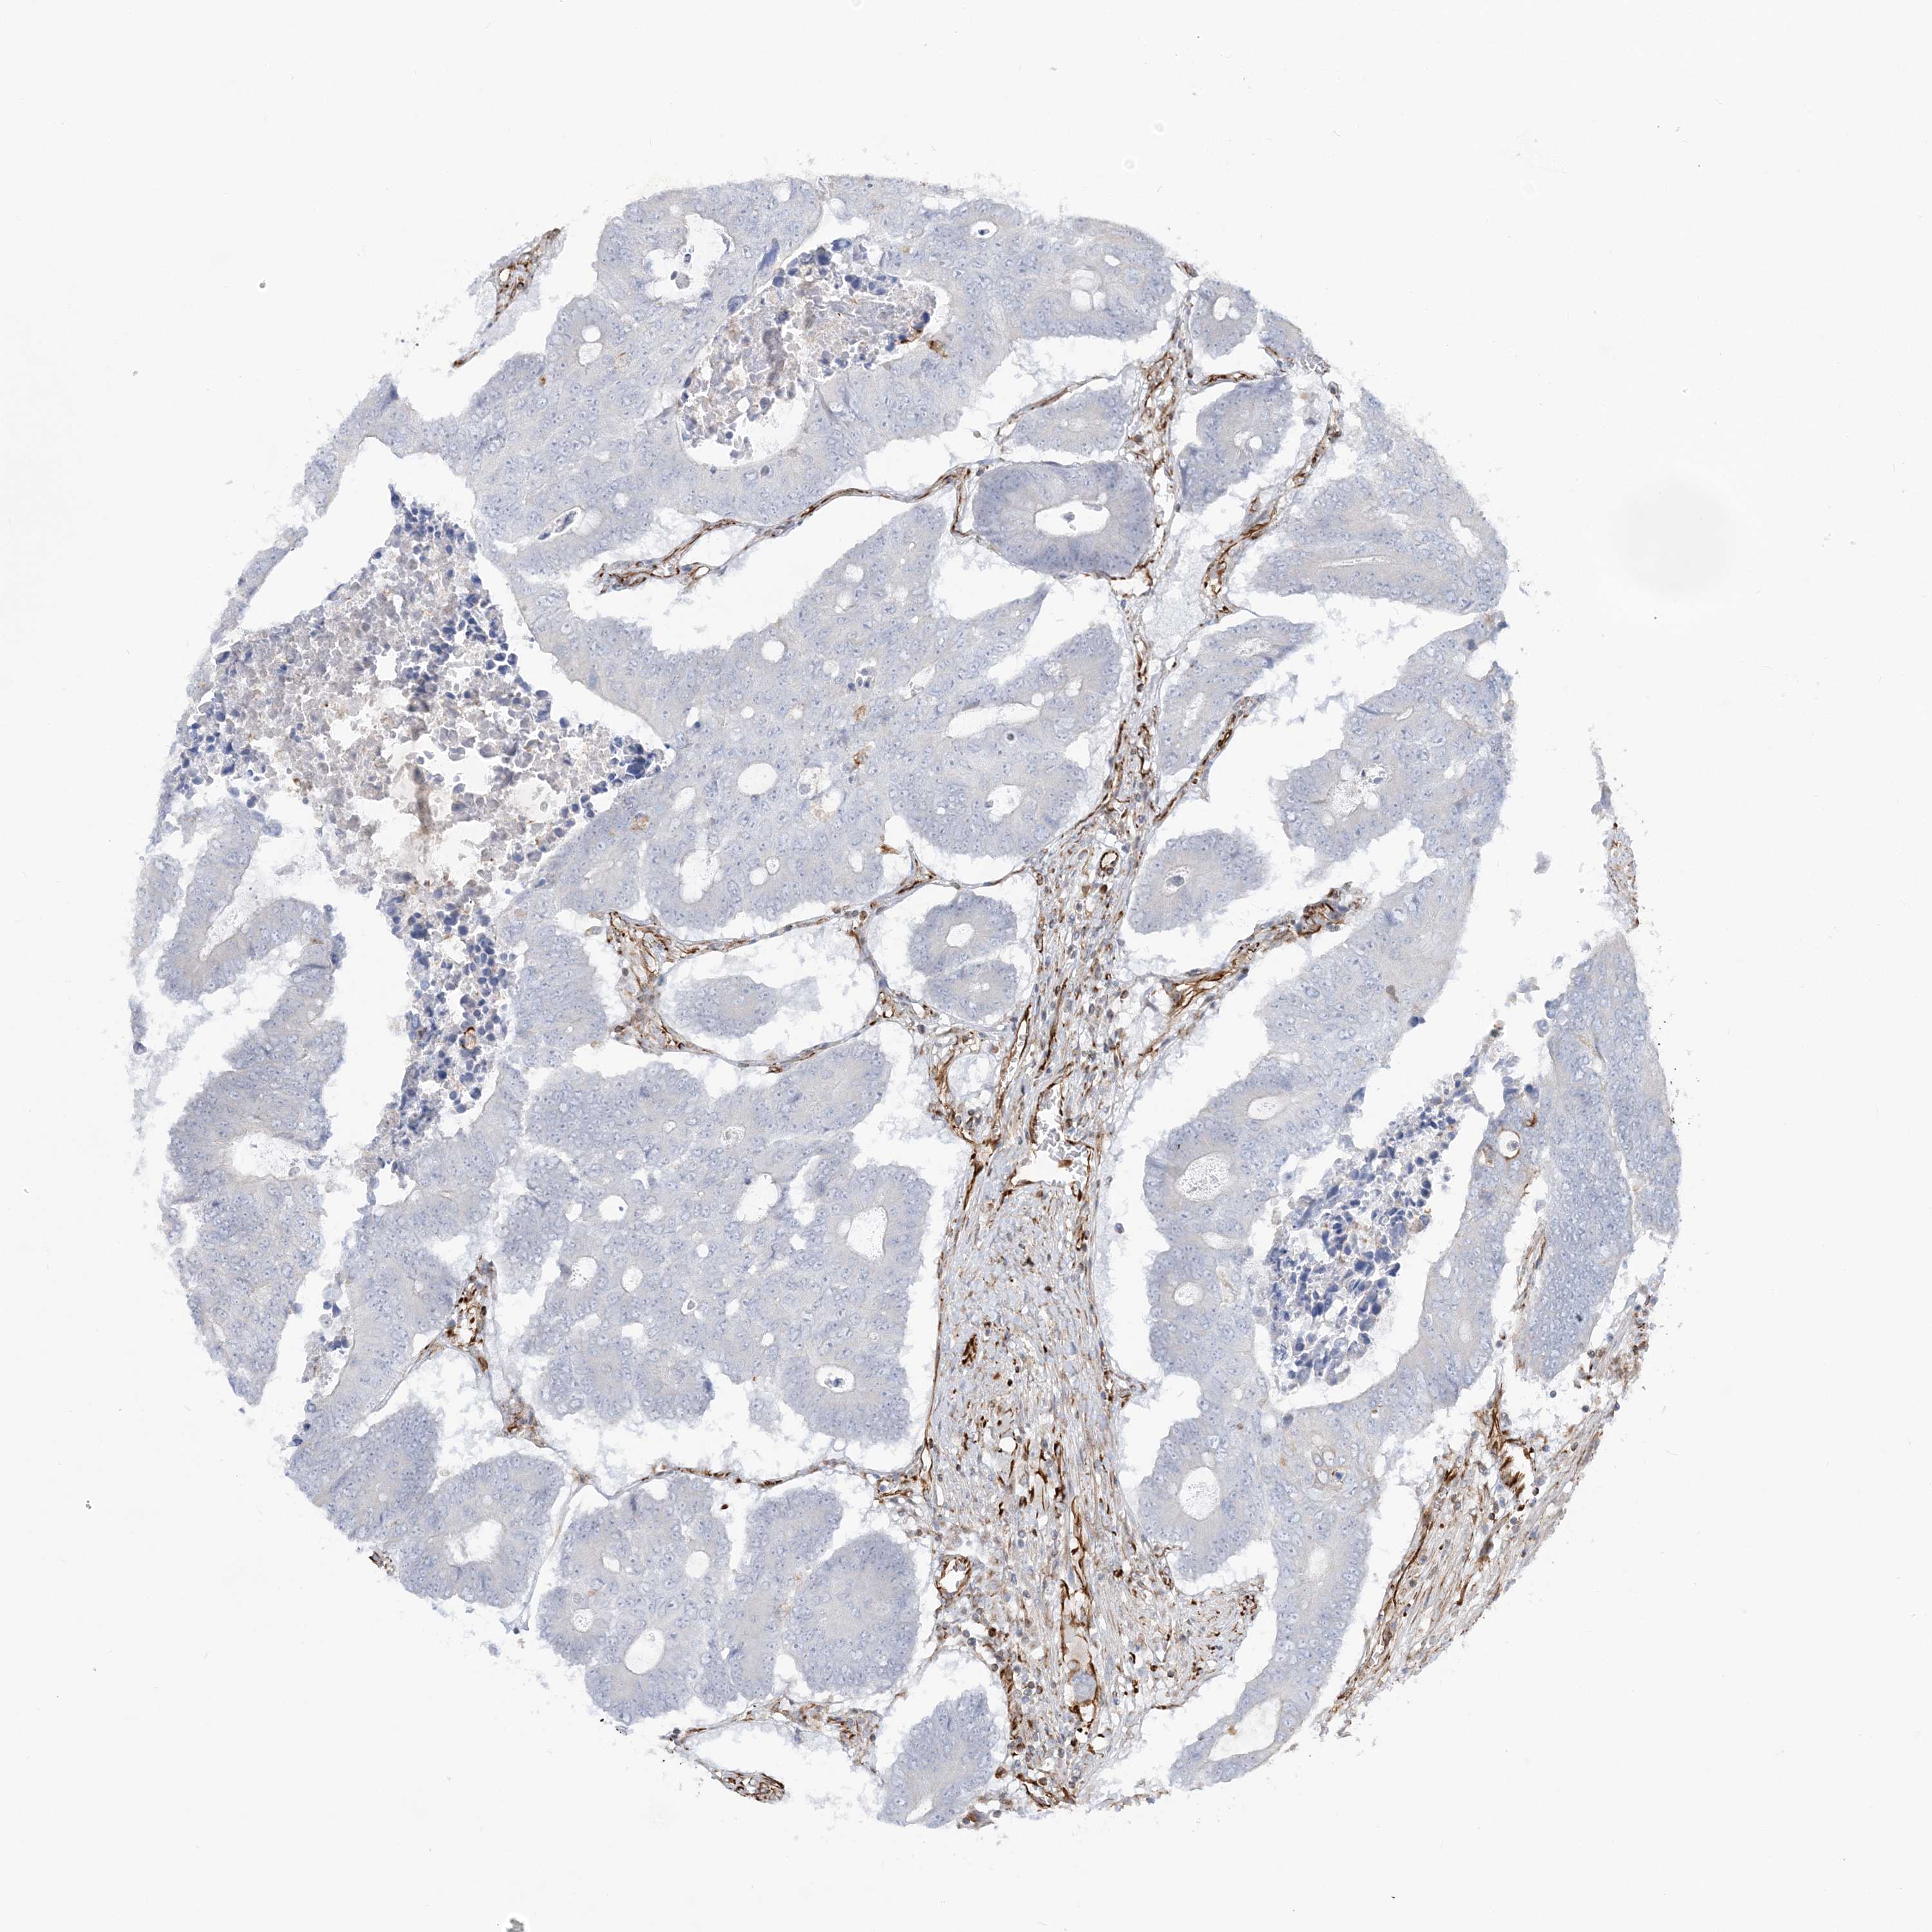

CANCER COLORECTAL CANCER Show tissue menu

Colorectal cancer

Human cancer

Colon adenocarcinoma